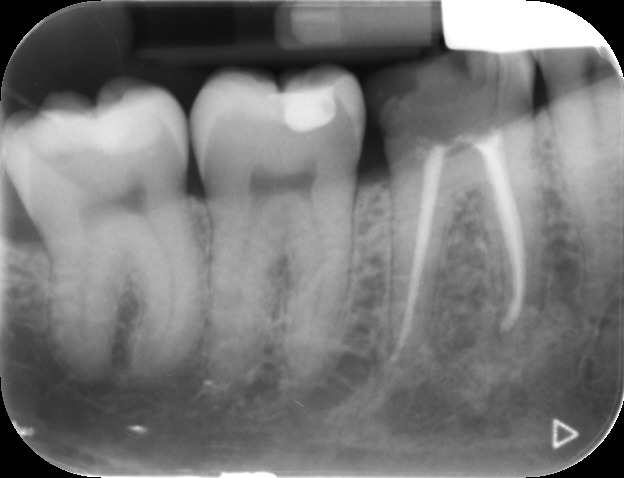

An access cavity is placed on the surface where the patient bites, to reach the root canals of the tooth. Once all the canals are identified, small files are used to remove the infected pulp.

Files of different sizes are used to eliminate bacteria and infection and to shape the canals. The canals are disinfected thoroughly with irrigants and later the canals will be sealed in 3 dimensions with a special medicament called gutta-percha to prevent reinfection of the tooth and the access cavity will be sealed with a temporary filling.